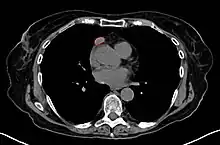

| An encapsulated thymoma (mixed lymphocytic and epithelial type) | |

When a thymoma is suspected, a CT/CAT scan is generally performed to estimate the size and extent of the tumor, and the lesion is sampled with a CT-guided needle biopsy. Increased vascular enhancement on CT scans can be indicative of malignancy, as can be pleural deposits.[2] Limited biopsies are associated with a very small risk of pneumomediastinum or mediastinitis and an even-lower risk of damaging the heart or large blood vessels. Sometimes thymoma metastasize for instance to the abdomen.[6]